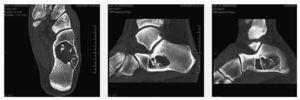

Un cop realitzat el diagnòstic es realitza tomografia computeritzada (TC) per tal de valorar l'estat de les corticals òssies (fig. 3).

Figura 3 Imatges coronal i sagitals en la TC.

La TC objectiva una lesió osteolítica amb àrees de densitat semblant al teixit adipós i extenses calcificacions o ossificacions. Les corticals es troben perfectament conservades i sense risc de fractura.